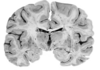

Label A&B [2] What structure do A & B make together? [1]

A: **Putamen** B: **Globus pallidus (internal and external capsule)** Together: **Lentiform nucleus**

Below is a coronal section of the cerebrum. Which of the following labels corresponds to an intrinsic nuclei of the basal ganglia? A B C D

Below is a coronal section of the cerebrum. Which of the following labels corresponds to an intrinsic nuclei of the basal ganglia? A B **C** D

191